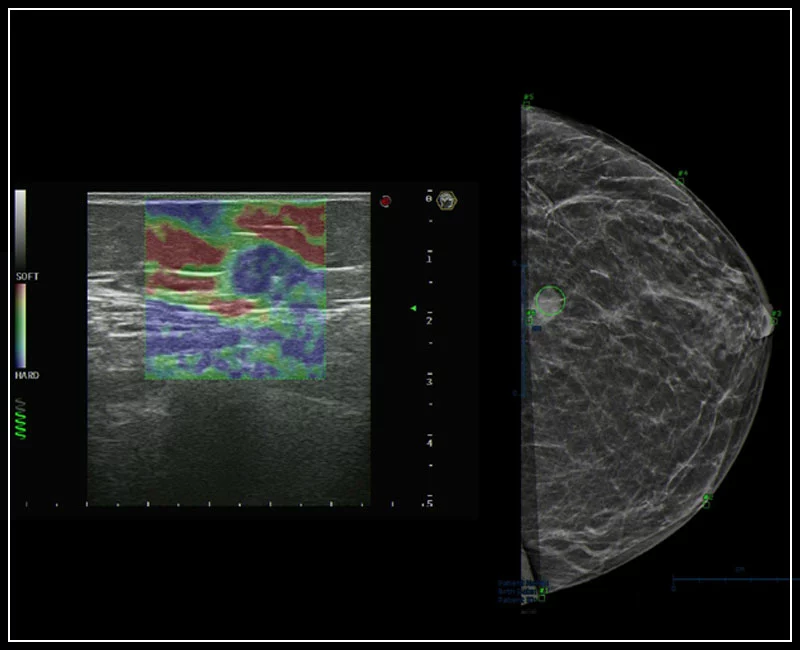

MyLab™9 Platform - Breast BodyMap and real-time ElaXto in Mammo

MyLab™9 Platform - Breast BodyMap and real-time ElaXto in Mammo